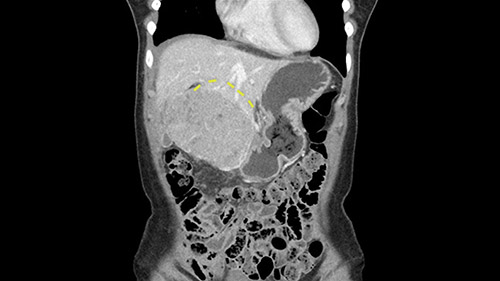

So if we look at the CT scan, on the axial, it’s a larger lesion. It’s about 6 or 7 or 8 centimeters. So it does look a bit threatening in terms of its resectability but if you really drill down deeply into the anatomy, and I think the coronal [imaging] is even better, you can see that the entire mass is on the patient’s left side of the falciform ligament. So it’s really only a left-sided tumor and not even really a left-sided tumor because Segment 4 is uninvolved anatomically.

None of the parenchyma is affected and this tumor is very exophytic; like many Hepatitis B hepatomas; and otherwise is resectable with either a wedge resection part of Segment 2-3 or a formal left lateral segmentectomy.

Some of my colleagues thought it may be involving Segment 4 and we’d need a formal left hepatic lobectomy, dividing anatomically: the left portal vein, left hepatic artery, left bile duct. But I didn’t think so, but you can see there is a challenge in terms of being certain where this tumor is located. So we’re prepared to do any of those 3 but my person view is that its going to be an exophytic tumor off of the left lateral segment and probably a wedge.

As I review the CT scan, we have both arterial and venous phases, the tumor is obvious. But I’ll start by saying that the liver itself does not appear to be cirrhotic to my eye. It’s got a normal contour and allied to that, that I do not see evidence of portal hypertension. The spleen is normal, there’s no collateral vessels. The tumor itself, I measured maximally at about 11 centimetres in diameter and I’m told the alpha fetoprotein is very high (over 10000), which is entirely consistent with this being a solitary hepatocellular carcinoma that is very exophytic. It seems to emanate off the inferior margin of Segment 3 (because that’s the falciform). I’ll start by saying that this is not transplantable. The tumor exceeds our guidelines for transplantation, but it's likely resectable based on normal liver and no portal hypertension.

So the issue with regards to resection. A left sided tumor. I believe I can see the falciform ligament right here so we’re looking at a resection of Segments 2, 3 of the left lobe of the liver. The left portal vein is right there. I think we’ll be wiser to take the left portal vein and therefore get well into Segment 4 and do a left hemihepatectomy. Certainly, one does not need to take the middle hepatic vein; it’s miles from the tumor.

The other thing I would do in this case is to certainly to assess the coronal phase as we can see in the coronal phase, this tumor looks like it's growing from Segment 3, and again I don’t think there’s involvement of the right side of the liver or even on Segment 4.